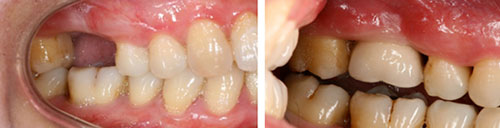

从功能上来讲,美容冠和种植牙就有不小的别,如果伴有牙齿不整齐、前凸、缺损等问题,或者属于重度的色素牙、氟斑牙,可以用美容冠的方式。对于有牙齿缺损等问题的人来说,既可起到修复的作用也能起到美白的作用,但是对于牙齿缺失的患者来说,种植牙则是比较好的选择了,种植牙是一套非常精密的模具中生产出来的,研发这套模具的成本高,而且种植体还要采用新型材料以便与牙槽骨更好地融合。

美容冠与种植牙并不相同,美容冠除了修复缺牙外,还可以用于修复变色、氟斑、釉质发育不全、锥形和部分缺损的前牙,对后牙大面积缺损修补后无法恢复牙齿形态等情况,也可以通过烤瓷牙这一来恢复牙齿的本来面目。

对于牙齿完全缺失的情况,我们还是建议做种植牙修复,种植牙有以下的优点: